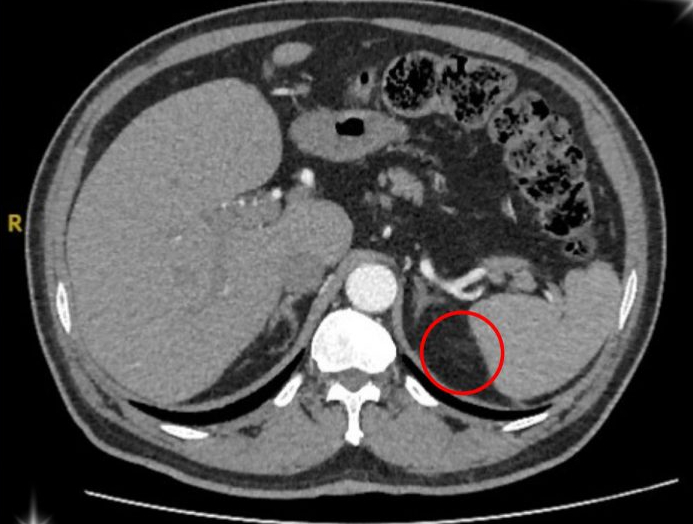

Hình ảnh vùng ổ bụng của bệnh nhân u tuyến thượng thận. Ảnh: BVCC

Sau quá trình kiểm tra kỹ lưỡng, ông T. được xác định mắc phải hội chứng Conn (hay còn gọi là cường Aldosterone tiên phát) – một bệnh lý hiếm gặp do khối u nhỏ ở vỏ tuyến thượng thận gây ra.